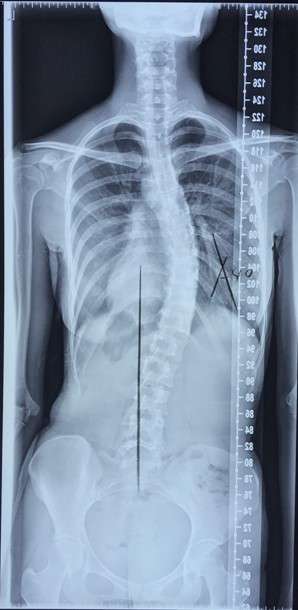

脊柱侧弯顾名思义,就是指脊柱向侧方发生了弯曲,但只有当这个弯曲大于10º的时候,我们就定义它为“脊柱侧弯”。

我们以常见的胸椎右侧弯为例(图7)。

患者自然坐位下的外观跟X光片是相符的,右侧胸廓较突出,左侧胸廓较凹陷。让患者双手自然下垂,左胸廓与左大臂之间的距离较大,右胸廓与右大臂之间的距离较小(图8)。

让患者自我调整端坐位,使鼻尖在肚脐的正上方。保持手臂原地不动,用左胸廓尽量去贴紧左大臂,让左侧的缝隙越小越好(图9)。

有的患者侧弯度数较小或柔韧性较好,轻轻用力就能做到过矫正(外观上看起来左侧胸廓较突出,右侧胸廓较凹陷);但有的患者度数较大或者柔韧性较差,尽管已经很努力了,可是看上去还是右侧胸廓较突出,左侧胸廓较凹陷。

这并不是问题,我们是跟原来的自己比,不要跟别人比。

只要我们的外观看起来比原来更对称一些就可以,运动幅度是可以慢慢练出来的。胸椎左侧弯的患者,同样的思路用右胸廓去紧贴右大臂即可。